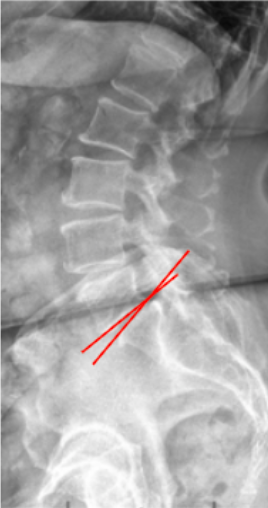

The Slip Angle, also known as the Lumbosacral Kyphosis Angle, quantifies the angular relationship between the inferior endplate of L5 and the superior endplate of S1. It measures the kyphotic deformity at the lumbosacral junction, particularly relevant in high-grade spondylolisthesis.

This angle reflects the degree of segmental kyphosis and helps determine instability severity and surgical reduction goals. A higher slip angle signifies increased anterior translation of L5 over S1, leading to greater sagittal malalignment and shear stress at the lumbosacral junction.

• Draw a line along the inferior endplate of L5.

• Draw another line along the superior endplate of S1.

• Extend both lines until they intersect.

• Measure the angle formed at their intersection—this is the Slip Angle (Lumbosacral Kyphosis Angle).

• The angle is typically measured anteriorly, opening toward the convex (kyphotic) side.